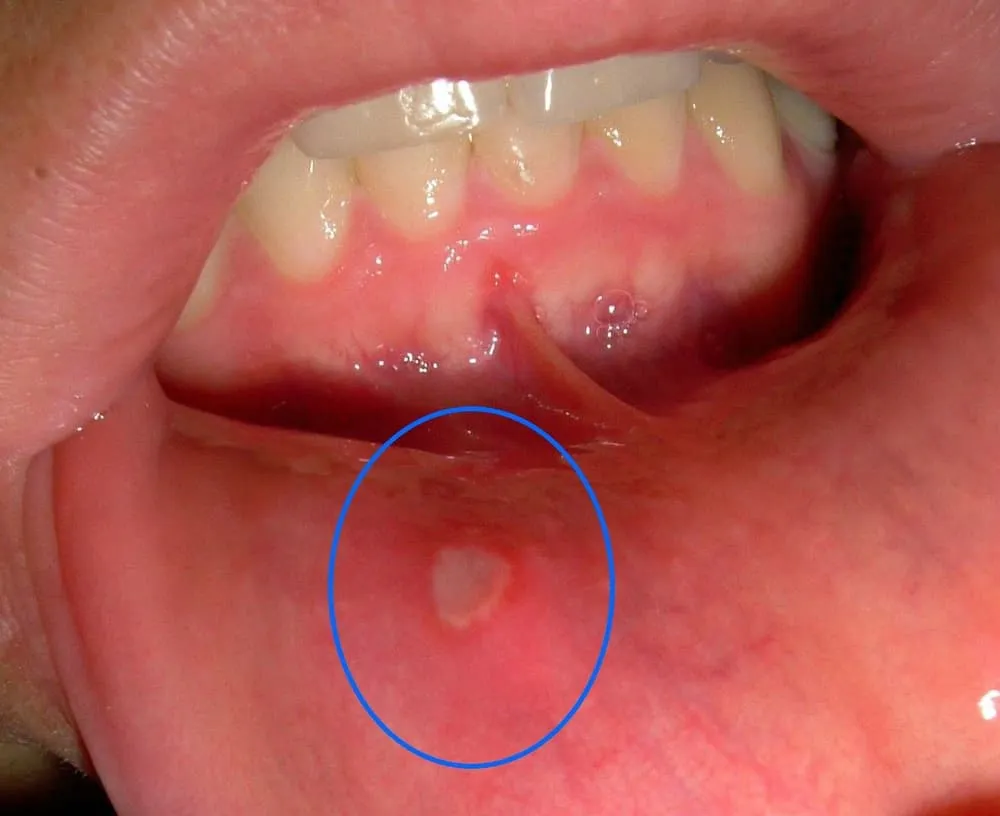

Afta na dziąśle to zazwyczaj niewielka, ale niezwykle bolesna zmiana. Jej wygląd jest dość charakterystyczny, co pozwala w większości przypadków na wstępną identyfikację. Typowa afta jest okrągłą lub owalną nadżerką, która jest wyraźnie odgraniczona od otaczającej ją zdrowej błony śluzowej. W jej centrum zauważysz białawy, szarawy lub żółtawy nalot, który jest niczym innym jak włóknikiem. Całość otoczona jest intensywnie czerwoną, zapalną obwódką, zwaną rumieniem. Najczęściej afty mają średnicę od 1 mm do 1 cm, choć zdarzają się również większe zmiany. Zazwyczaj pojawiają się na ruchomej części błony śluzowej dziąsła, bliżej policzka lub wargi, rzadziej bezpośrednio przy zębach.

Kluczowe cechy wizualne afty:

- Kształt: Okrągły lub owalny.

- Kolor nalotu: Białawy, szarawy lub żółtawy w centrum.

- Obwódka: Intensywnie czerwona, zapalna.

- Granice: Wyraźnie odgraniczona od otoczenia.

- Lokalizacja: Najczęściej na ruchomej błonie śluzowej dziąsła.

- Wielkość: Od 1 mm do 1 cm, rzadziej większe.